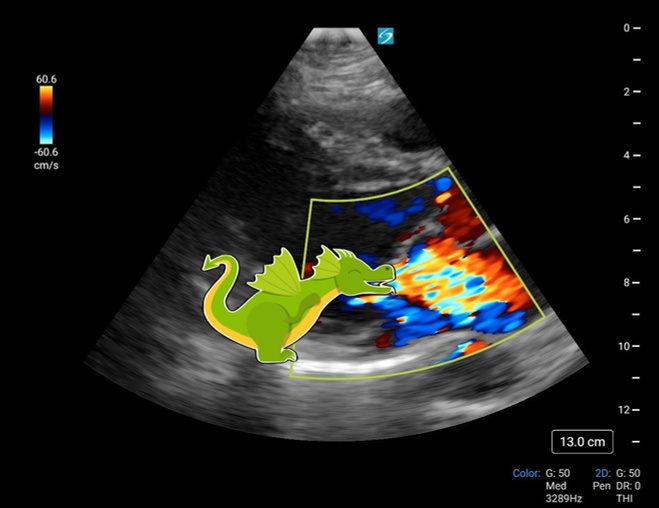

Jet de dragon?

Peu importe l'image qui vous permet de décrire une régurgitation, cette page tentera d'éclaircir la base et de vous initier à la recherche de régurgitation (sévère).

L'analogie du crachat de feu d'un dragon provient de l'une de mes résidentes et je l'adore! Pour ceux ne vivant pas dans un monde de princesse et de dragon, une diarrhée explosive au Mexique est une autre image probante. Je vous laisse choisir.

Un jet commence généralement petit à la valve puis s'agrandit de forme +/- triangulaire pour donner la forme classique.

Demeure, des jets atypiques existent:

Les jets excentriques qui suivent le rebord d'une structure (souvent l'oreillette en s'enroulant dessus).

Les jets diffus où la valve est en fait une passoire laissant passer une quantité massive de régurgitation et cela diffusément.